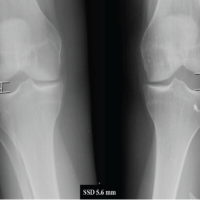

We present a case of a 68-year-old gentleman, a known epileptic for the past 15 years. Following a significant epileptic episode, he encountered abrupt and intense pain in both hip joints while in bed during the night. Subsequent to the episode, he found himself unable to mobilize or elevate his legs. A subsequent examination by his family physician the following morning prompted a portable X-ray, which suggested bilateral femoral neck fractures. The patient, under consistent anti-epileptic therapy (Tab Eptoin-Phenytoin and Tab Levera-Levetiracetam) for the past 15 years, had been seizure-free for the preceding 12 years. Approximately 3 months before the incident, a neuro-physician, assessing his condition, conducted an EEG with normal results, recommending a discontinuation of medication. On general examination, evidence of a tongue bite indicated a seizure during sleep. Although his MRI brain exhibited age-related atrophy without significant pathology, he was referred to our orthopedic department for further management. At the time of presentation, the patient was conscious, cooperative, and well orientation, with both limbs in adduction and external rotation. He experienced tenderness in the groin and significant pain on movement of both the hips, with no neurological or vascular deficits. Pelvic AP radiographs revealed Garden type IV transcervical neck of femur fractures with comminuted greater trochanter fractures in both hips. Despite having no previous hip pain and an active lifestyle, maintaining full functionality with weight-bearing. The severe displacement of hip fractures, delayed presentation, combined with his age and quality of bone, led us to anticipate a failure of osteosynthesis. Consequently, we planned bilateral total hip replacement surgery. Following thorough counseling with the patient and his family, staged bilateral hip replacement surgeries were proposed. Femur canal was Dorr B type, and pre-operative templating and planning led to the selection of uncemented prostheses (although cemented implants were kept backup) with a Ceramic on Poly bearing [3]. Comminuted fractures of the greater trochanter on both sides were addressed using two Tension band wires and non-absorbable supplementary Ethibond no. 5 sutures. The surgical procedure involved an anterolateral approach, utilizing a 32mm diameter head for the Pinnacle Poly constrained acetabular liner with a 50 mm outer shell diameter (DePuy, Warsaw, IN, USA) and a size 15 Corail cementless stem in the left hip. Subsequently, after a 5-day interval, the right hip underwent a similar procedure with similar implants. Both intraoperative and post-operative periods transpired without complications. Fig 2.

In adults with normal bone structure, the occurrence of bilateral femoral neck fractures is an infrequent phenomenon, typically necessitating substantial external force such as a motor vehicle accident or a fall from a considerable height [1]. While violent muscle contractions during seizures are recognized to cause fractures or dislocations, with an incidence of 1.1% following a convulsion [2], the musculoskeletal consequences of seizures extend beyond the conventional posterior shoulder dislocation. However, there are notably scarce documented cases of bilateral hip fractures occurring during seizures [4,5]. Literature underscores that individuals with epilepsy face an elevated fracture risk, with an increased likelihood of two- to six-fold [6]. Notably, certain anti-epileptic drugs, particularly Phenytoin, are known to alter calcium metabolism, potentially inducing osteomalacia or reducing bone density during prolonged treatment. This elevates the susceptibility to pathological fractures, emphasizing the importance of monitoring bone mineral density in patients using anti-epileptic drugs [7]. Our patient, under long-term anti-epileptic therapy, had been receiving Vitamin D and calcium supplements, with initial values on admission indicating a Vitamin D level of 26.6 and a calcium level of 8.9. Histopathological examination of the femoral head specimen revealed normal bone histology. Recommendations by Pack et al advocate for Vitamin D and calcium supplementation, alongside vigilant monitoring of bone mineral density, especially in individuals undergoing prolonged antiepileptic treatment, particularly if they present with concurrent bone pathologies [8]. For patients under the age of 60, internal fixation of femoral neck fractures represents the standard of care, while arthroplasty procedures tend to be reserved for the elderly population or specific clinical scenarios [9,10]. In cases where inadequate reduction is achieved following femoral neck fractures, the risk of osteosynthesis failure becomes particularly concerning. However, the current evidence base has not established a definitive correlation between the timing of fixation and the subsequent development of osteonecrosis of the femoral head [11]. Duckworth et al. have identified a direct association between comorbidities compromising bone quality and fixation failure in displaced femoral neck fractures among the young adult demographic. Their findings suggest individuals over 40 years exhibiting compromised that bone integrity may warrant consideration for primary total hip arthroplasty given the heightened predisposition to fixation failure [12]. For this particular patient, the decision to undertake staged uncemented bilateral constrained total hip arthroplasties using anterolateral approach was predicated on several key considerations: The patient’s chronological age, the presence of an epileptic disorder, the prospective risk of developing post-operative aseptic osteonecrosis of the femoral heads, and the anticipated necessity for future revision procedures. It warrants highlighting that the rates of instability and dislocation following total hip arthroplasty undertaken for femoral neck fractures notably surpass those encountered in arthroplasty procedures performed for the treatment of degenerative osteoarthritis [15]. This risk is further compounded in patients with recurrent seizure disorders. Primary total hip arthroplasty in the setting of cognitive deficits or neuromuscular diseases has been associated with notable post-operative dislocation rates; hence, constrained liner or dual mobility hip arthroplasty is recommended in such cases [16,17]. In our surgical approach, we employed anterolateral exposures to circumvent violation of the posterior capsule and musculature, thereby mitigating dislocation risk [18-20]. Moreover, the utilization of constrained acetabular liners aimed to confer stability is a pivotal consideration in patients with a history of recurrent dislocations. Constrained acetabular components, renowned for their efficacy in preventing instability without substantially compromising implant longevity, were judiciously selected to optimize the durability of the arthroplasty constructs [21,22]. (Fig 3 & 4).